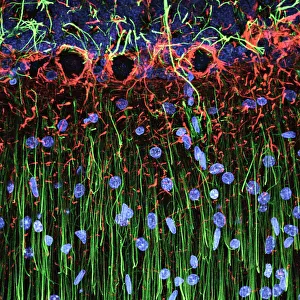

The central nervous system, the intricate network that governs our every thought and movement, is a marvel of complexity. From the delicate cerebellum tissue to the detailed light micrograph capturing its essence, we are reminded of its importance in maintaining balance and coordination. Anatomy comes alive as we explore the human brain from an inferior view. The intricacy of brain fibers is revealed through DTI MRI scans like C017/7099 and C017/7035, showcasing their vital role in transmitting information throughout this extraordinary organ. Artistic renderings bring us closer to understanding the medulla oblongata's significance within the brain. Its portrayal in various artworks allows us to appreciate how it controls essential functions such as breathing and heart rate. As we delve deeper into studying the central nervous system, models of the human brain provide invaluable insights into its structure and organization. Lateral views reveal countless regions responsible for cognition, emotion regulation, sensory perception, and motor control. Microscope slides offer glimpses into nerve cells' intricate architecture—a testament to their ability to transmit electrical signals at lightning speed. Meanwhile, glial stem cell cultures captured under a light microscope remind us of their crucial role in supporting neuronal function. Finally, artistic representations unveil the limbic system's enigmatic nature—an interconnected web responsible for emotions and memory formation. These captivating artworks allow us to visualize this complex network within our brains. Exploring these hints provides a glimpse into the awe-inspiring world of our central nervous system—the very foundation upon which our thoughts, actions, memories reside—reminding us just how remarkable our brains truly are.